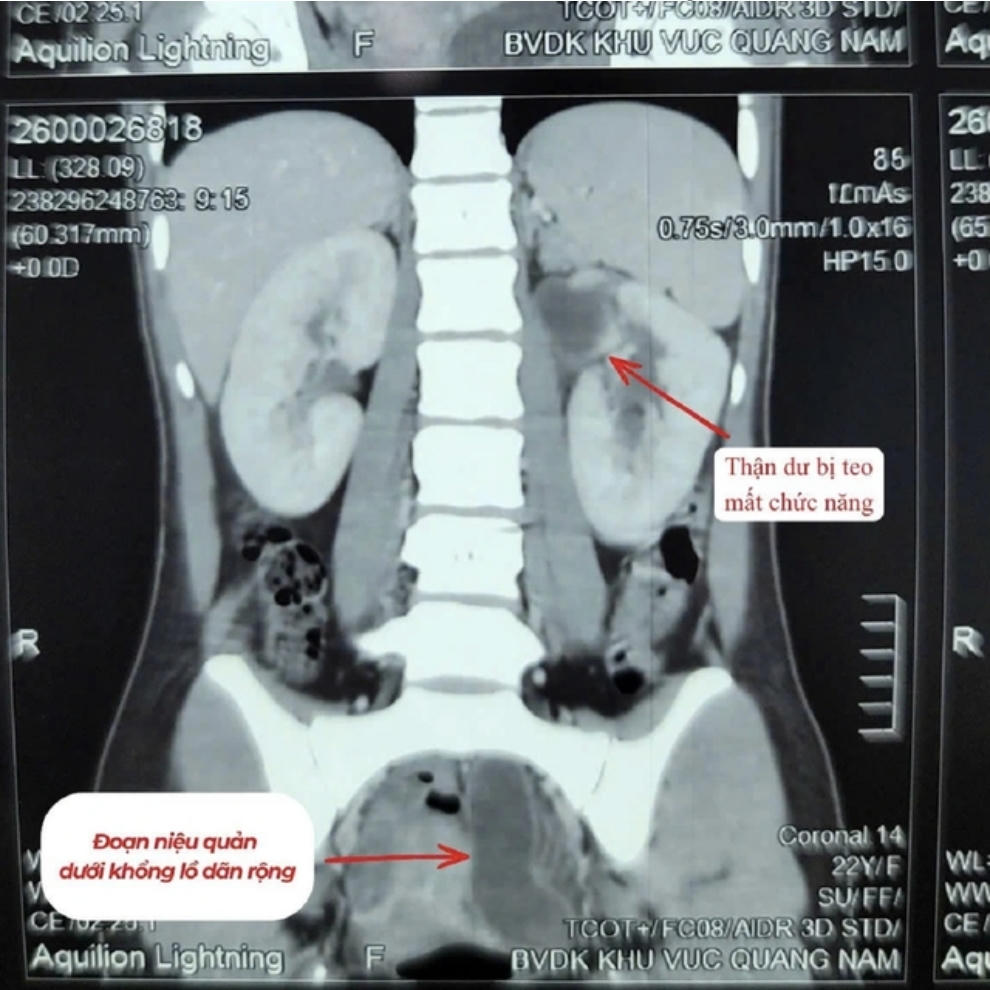

Qua thăm khám và xét nghiệm, bác sĩ xác định người bệnh có hai thận bên trái (tổng cộng 3 thận), trong đó một thận đã mất chức năng, niệu quản giãn lớn và chứa nhiều mủ – nguyên nhân gây nhiễm trùng nghiêm trọng.

Sau khi hội chẩn, ê-kíp đã phẫu thuật cắt bỏ toàn bộ thận và niệu quản bên trái đã hỏng nhằm loại bỏ ổ nhiễm trùng.